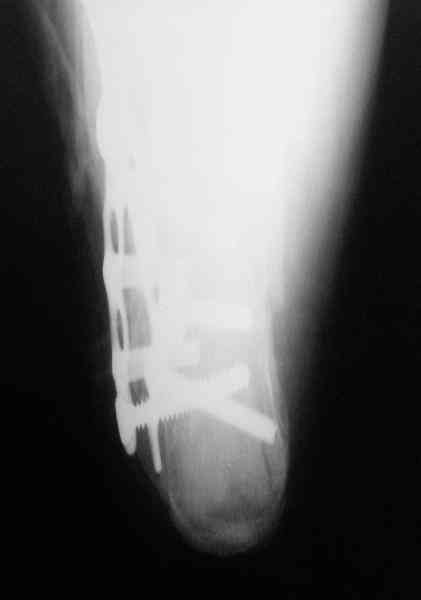

Пяточной пластиной

С уважением, А.Семенистый.

ГКБ № 13, Москва.

Какой предпочитаете доступ? Нет ли показательных рентгенснимков?

Открытый и закрытый способы лечения.

MOST OF MY COLLEGUES WOULD OPEN IT LATERALLY( a flap) and having a proper reduction would put a plate.

Перелом безусловно внутрисуставной. Киста-не киста принципиального значения не имеет.

Имея какой-то опыт остесинтеза пяточной кости пластинами пришли к выводу - где есть альтернатива лучше без нее, где нет значит пластина и долгие переживания в ожидании очередной перевязки. Может нам так не везло, но и одного некроза( слава богу без остеомеилита) достаточно, чтобы призадуматься.